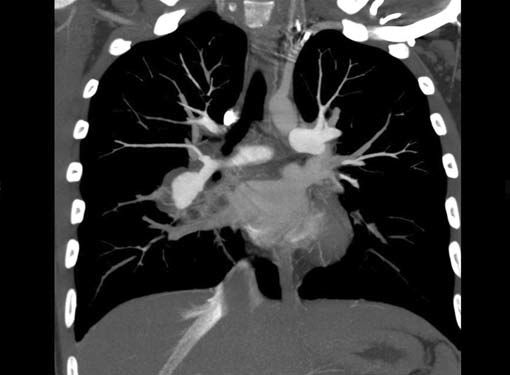

Filling defects (Figs 16A and B) may be seen in main

pulmonary artery (MPA), left pulmonary artery (LPA) and

right pulmonary artery (RPA), interlobar artery, segmental

divisions (Figs 17A and B). On occasions, detection in distal

parts of segmental divisions is difficult. This can be further

confounded by motion artifacts, non- or minimally opacified

accompanying pulmonary veins.